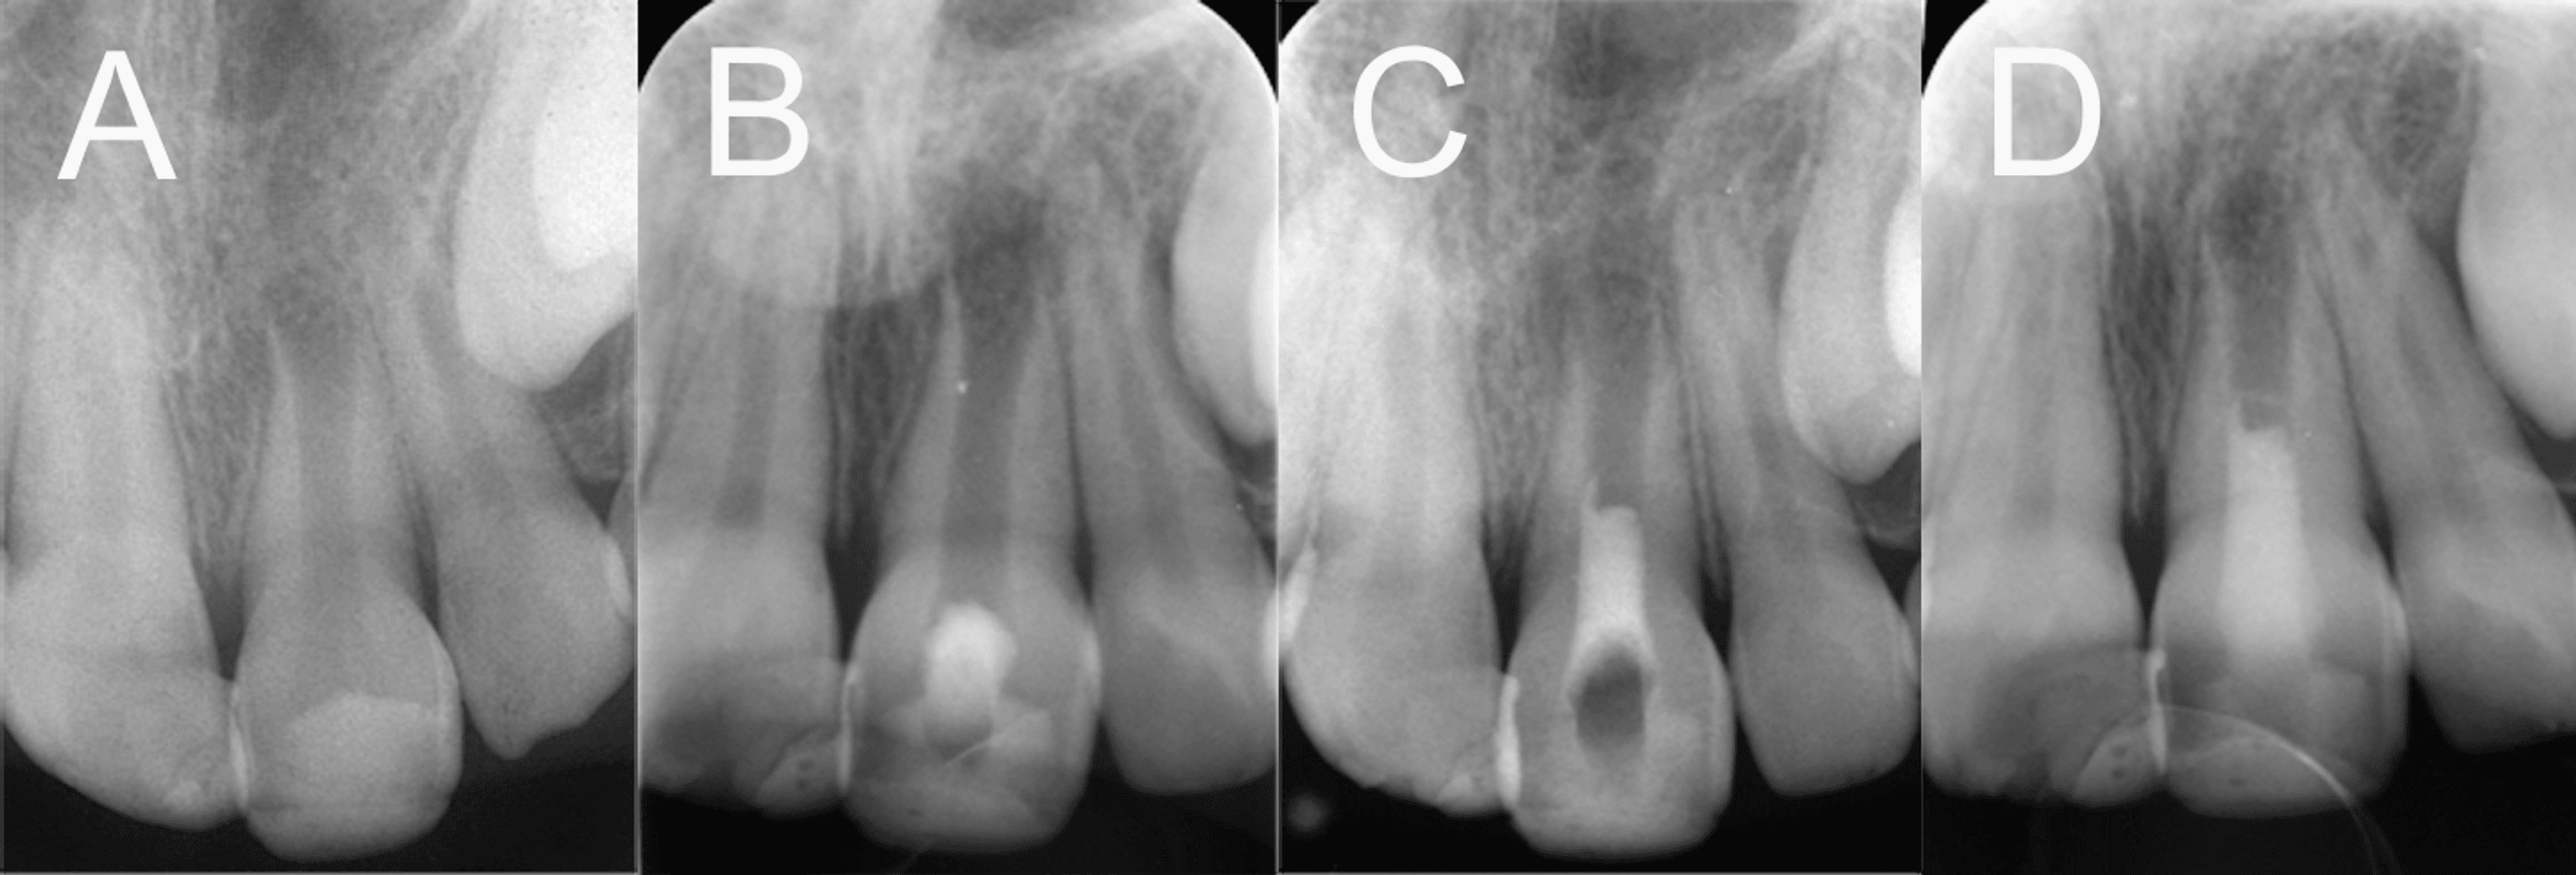

Figure 2 from / CASO CLINICO Regenerative endodontic treatment options